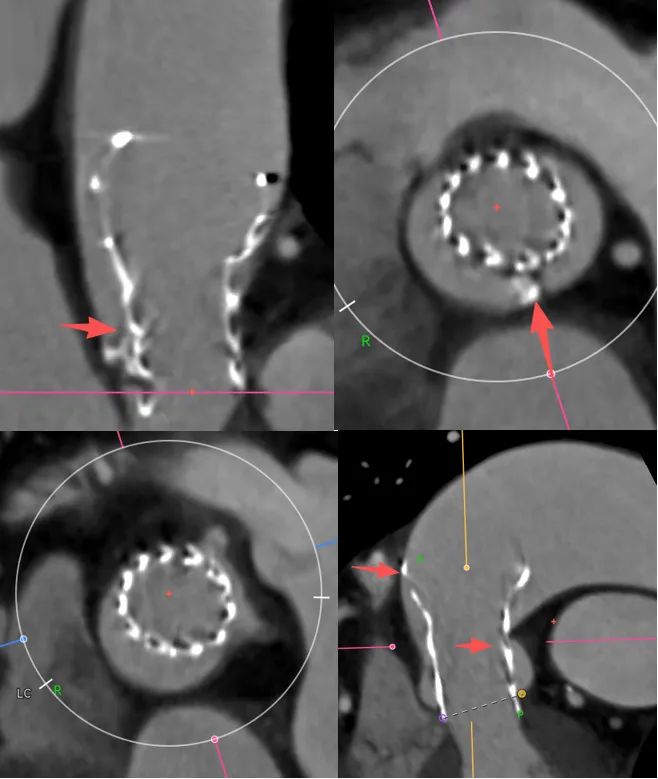

结合下图术后CT可以看到,我对瓣膜位置的预判基本正确,钙化与升主的限制共同把瓣膜推向小弯侧,这时候可以看到瓣膜距离冠脉开口非常之近,如果再贴近一点,瓣膜植入再高一点,裙边或者吊桥可能会有冠脉阻挡风险。所以像这种单边钙化的冠脉风险也是需要看看的。

在这个病例中,我们能够看到升主对于瓣膜的推挤还是很大的,我们既往对于升主的长度有些人会用来评估同轴性,但是很多喜欢量中间来跟支架长度作对比,但实际上要量大弯侧边缘的到转弯地带的长度。

另外还可以看到二叶瓣的瓣膜植入进去,实际上瓣环那边是空的,虚拟瓣环没有任何锚定和封堵作用,实际上的锚定和封堵都是靠瓣上空间。二叶瓣的瓣膜选择需要抛弃依赖瓣环这个习惯。要综合考虑瓣上限制,过大oversize会导致框架扩张不充分(内折或者过度压缩)、瓣叶卷曲等影响血流动力学。笔者一直很反对过度的oversize。